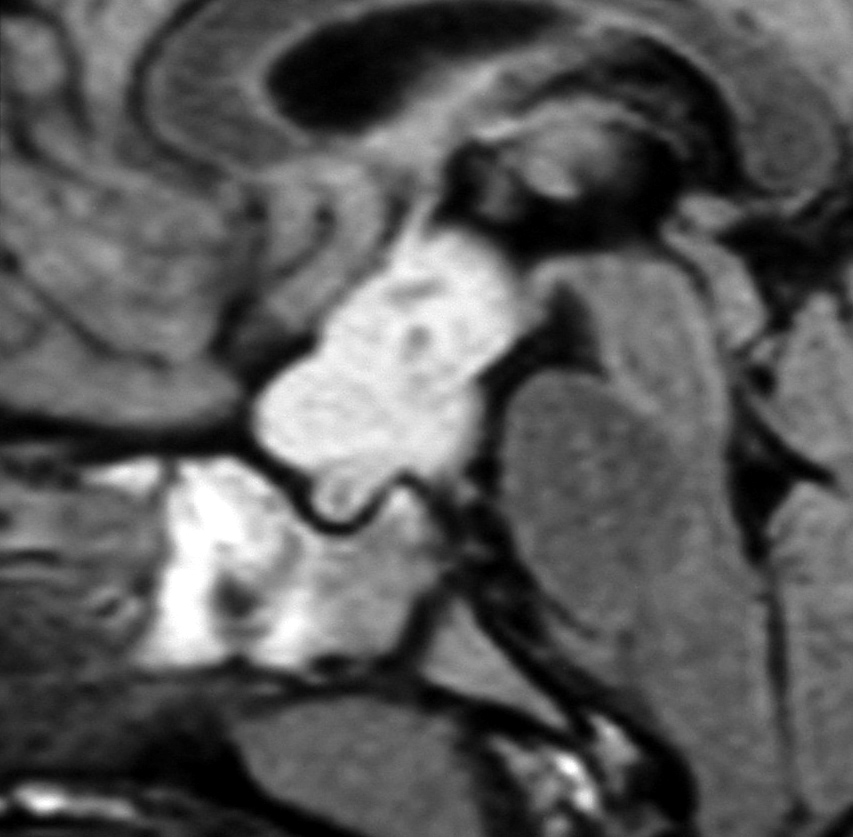

化学療法が有効なのは,上の画像のようにガドリニウム増強で強く増強されるタイプです,またT2強調画像で強い高信号になるものほど化学療法が有効です,要するに毛様粘液性星細胞腫の要素に化学療法が有効であるということです

この毛様細胞性星細胞腫はガドリニウムでほとんど増強されません(右側のMRI)から,化学療法を行っても小さくなりませんので,手術摘出する必要があります,実際に視床下部から発生したもの視交叉が犯されておらず,手術亜全摘出できました